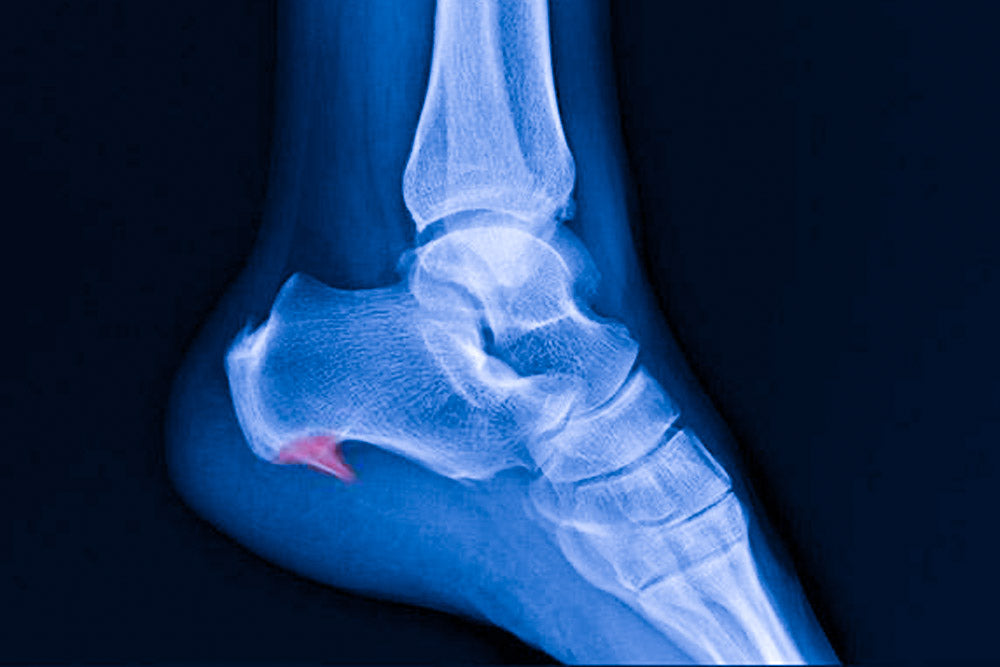

L'épine sous le pied, également connue sous le nom d'épine calcanéenne, est une affection douloureuse qui peut toucher tout le monde. Il s'agit d'une inflammation autour du talon ou de l'aponévrose plantaire qui provoque un sentiment dérangeant et parfois insupportable. Dans cet article, nous vous présentons différentes façons de soulager ce problème sans avoir à passer par une intervention invasive.

Identifier l'épine sous le pied

Pour apporter les solutions les plus adaptées, la première étape consiste à identifier l'épine sous le pied et ses causes possibles. Plusieurs facteurs peuvent entraîner cette douleur, tels que :